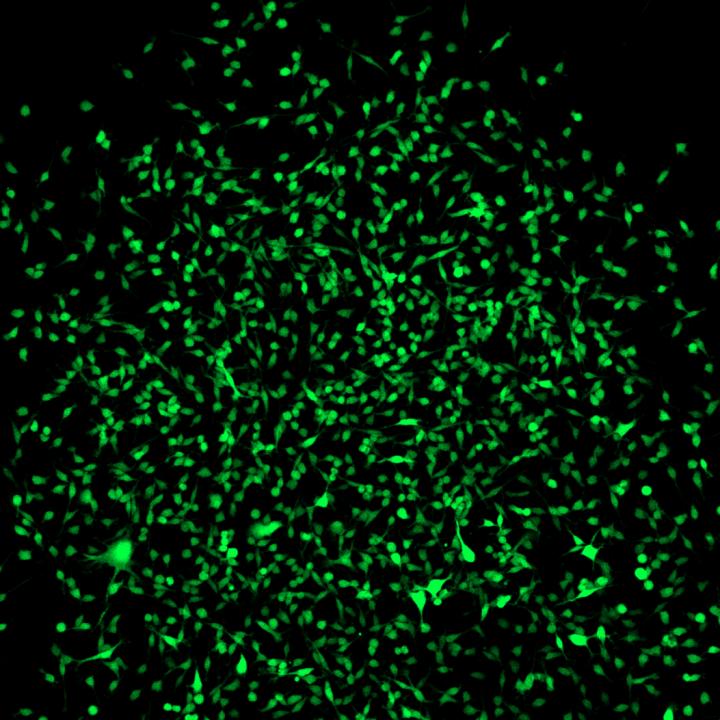

New mouse model makes stem cells light up green

Multipotent stromal cells have long been a hot topic in medical research. Scientists at the University of Bonn have now found a way to specifically mark these stem cells. This makes it possible to analyze their distribution pattern and their function in living organisms. The study, which included researchers from Oxford University, Tsukuba University and the Karolinska Institute Stockholm, is now being published in the journal Cell Stem Cell .

They then generated transgenic mice, where expression of the CD73 gene results in green fluorescent labeling of the respective cell. "As CD73 is mainly active in the multipotent stromal cells, these are marked by a green glow", explains Breitbach's co-author Dr. Kenichi Kimura.

The dye-labeling made it possible to isolate these cells from the bone marrow. The scientists were then able to show that bone, fat and cartilage cells differentiate from a single multipotent stromal cell in the culture dish. "Our method makes it possible to examine the cells in their original state", says Breitbach. "In future studies, it will for example be possible to clarify directly in the living animal whether and how the stem cells migrate to the different organs in the case of injury or illness, and what they do there."